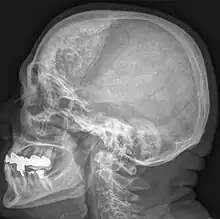

Hyperostosis frontalis interna in a 74-year-old woman

Hyperostosis frontalis interna is a common, benign thickening of the inner side of the frontal bone of the skull. It is found predominantly in women after menopause and is usually asymptomatic. Mostly frequently it is found as an incidental finding discovered during an X-ray or CT scan of the skull.